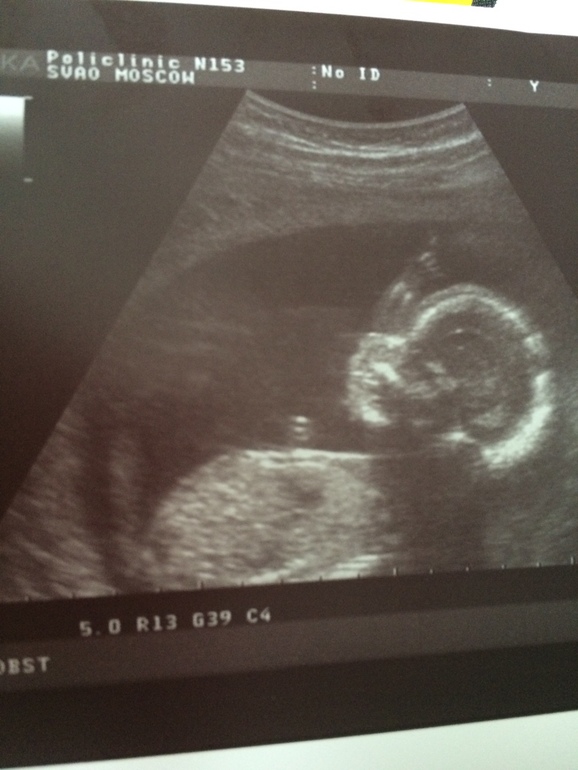

Второе УЗИ, или конец интригам ))

Пол малышаСегодня ходили на второе скрининг, даже папу нашего пустили. Все хорошо у малыша, развивается по сроку, все на своих местах (точные циферки узнаю только на следующем приеме). Срок 18+6

И нам сказали, что растет и копошится там наша маленькая девочка. Дочка. Сонечка.